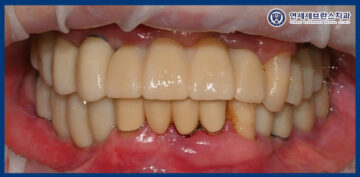

25.10.23

이렇게 치료를 마무리한 후,

약 3개월 뒤 환자분께서 내원하시어

정기 검진을 진행하였습니다.

검진 결과 임플란트와 주변 잇몸 상태

모두 특별한 이상 없이

안정적으로 유지되고 있었으며,

일상생활에서도 불편함 없이

잘 사용하고 계신 것을

확인할 수 있었습니다.

또한 안내해 드린 임플란트 관리 방법도

꾸준히 잘 실천해 주고 계셔서,

임플란트 주위 잇몸 역시

건강한 상태를 유지하고 있었습니다.

환자분께서는 오른쪽으로 씹는 걸 포기하고 살았는데

임플란트 이후 마음대로 먹을 수 있게 되어

너무 만족하게 되셨다고 하셨습니다.